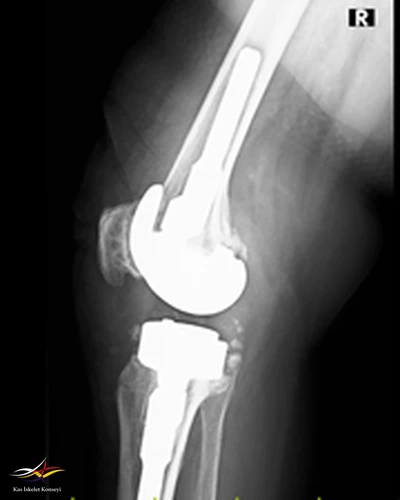

Resim 4. Revizyon ameliyatı sonrası lateral direkt grafi.